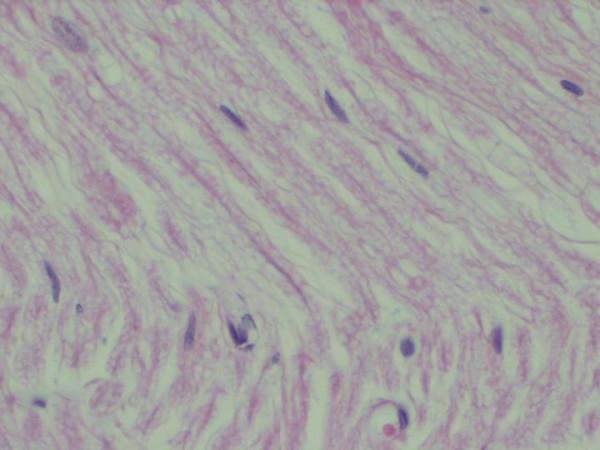

70 adult male rats were randomly divided into 5 groups in part 1 experimentation and 3 groups in part 2 experimentation. A rat model of severe nerve ischemia which was produced by tying iliac arteries and all identifiable anastomotic vessels with a silk suture (6-0) was used to study the effects of I/R and IP on nerve biochemistry. The suture technique used was a slip-knot technique for rapid release at time of reperfusion in the study. Cytoplasmic vacuolar degeneration was also histopathologically evaluated by light microscopic examination in sciatic nerves of rats at 7th day in part 2 study.

3 hours of Reperfusion resulted in an increase in nerve malondialdehyde levels when compared with ischemia and non-ischemia groups (p < 0.001 and p < 0.0001 respectively). IP had significantly lower nerve MDA levels than 3 h reperfusion group (p < 0.001). The differences between ischemic, IP and non-ischemic control groups were not significant (p > 0.05). There was also a significant decrease in vacuolar degeneration of sciatic nerves in IP group than I/R group (p < 0.05).

IP reduces the severity of I/R injury in peripheral nerve as shown by reduced tissue MDA levels at 3rd hour of reperfusion and axonal vacuolization at 7th postischemic day.